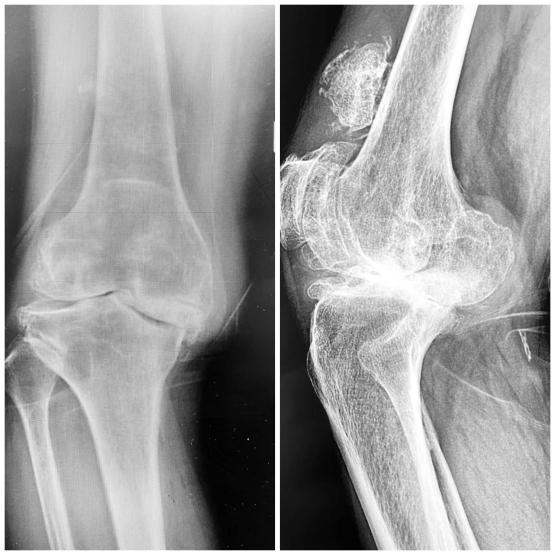

兰大二院西固医院骨科团队,于2021年12月31日开展西固区首例导航(IKPAS)下膝关节膝关节置换术(TKA),该患者严重膝关节畸形,生活重度受限,术后患者畸形完全纠正,康复良好,生活质量明显提高。导航(IKPAS)下关节置换技术为当今先进手术技术,此技术为严重膝关节畸形患者力线纠正带来了福音。